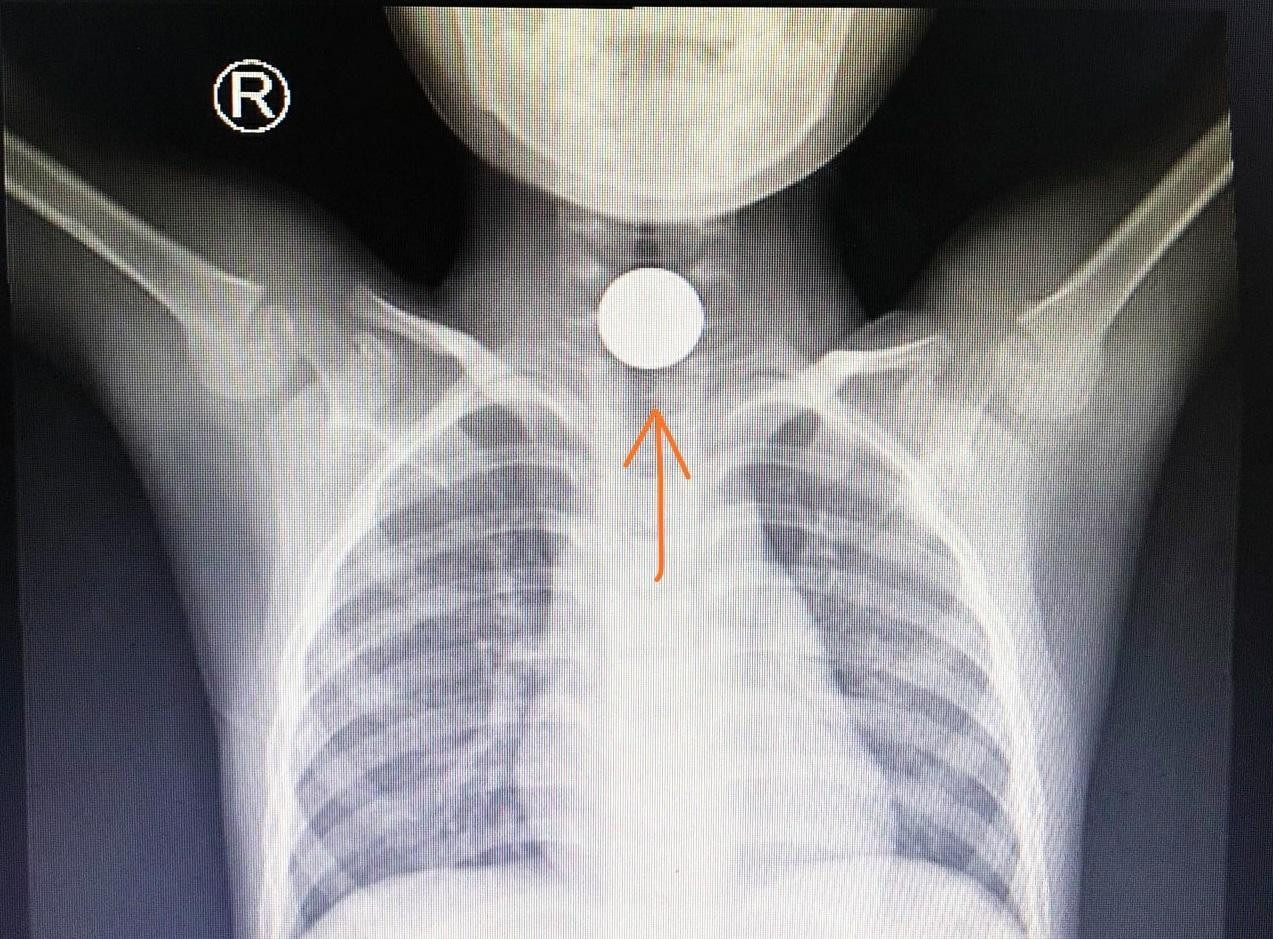

Một trường hợp khác là bé trai 5 tuổi nhập viện trong tình trạng đau tức ngực, khó thở. Khai thác bệnh sử của các bác sĩ từ phía gia đình ghi nhận, trước đó bé được lì xì 1 đồng xu vàng may mắn. Thích thú với món quà vừa nhận, cậu bé đã ngậm vào miệng chơi. Trong lúc đang nô đùa cùng các bạn, bé bất ngờ bị ho sặc, khó thở, ôm cổ họng.

Ngay lập tức, bé được chuyển đến Bệnh viện Nhi Đồng Thành Phố cấp cứu. Trên hình ảnh kiểm tra, bác sĩ phát hiện, đồng xu đang mắc ngang, bít thực quản đoạn trên của bệnh nhi. Ngay lập tức, các bác sĩ đã tiến hành nội soi gắp thành công dị vật ra ngoài.

BS Lê Đức Lộc, Trưởng ê kíp nội soi cho biết, bệnh nhi bị hóc dị vật đường thở có thể dẫn tới suy hô hấp cấp, nguy kịch tính mạng. Bệnh nhi hóc dị vật thực quản và đường tiêu hóa nếu không được xử lý đúng và kịp thời sẽ bị loét, rò thủng thực quản và viêm loét dạ dày với nhiều hệ lụy khó lường. Nguy hiểm hơn, lâu ngày sẽ làm tổn thương, thậm chí là thủng thực quản dạ dày.